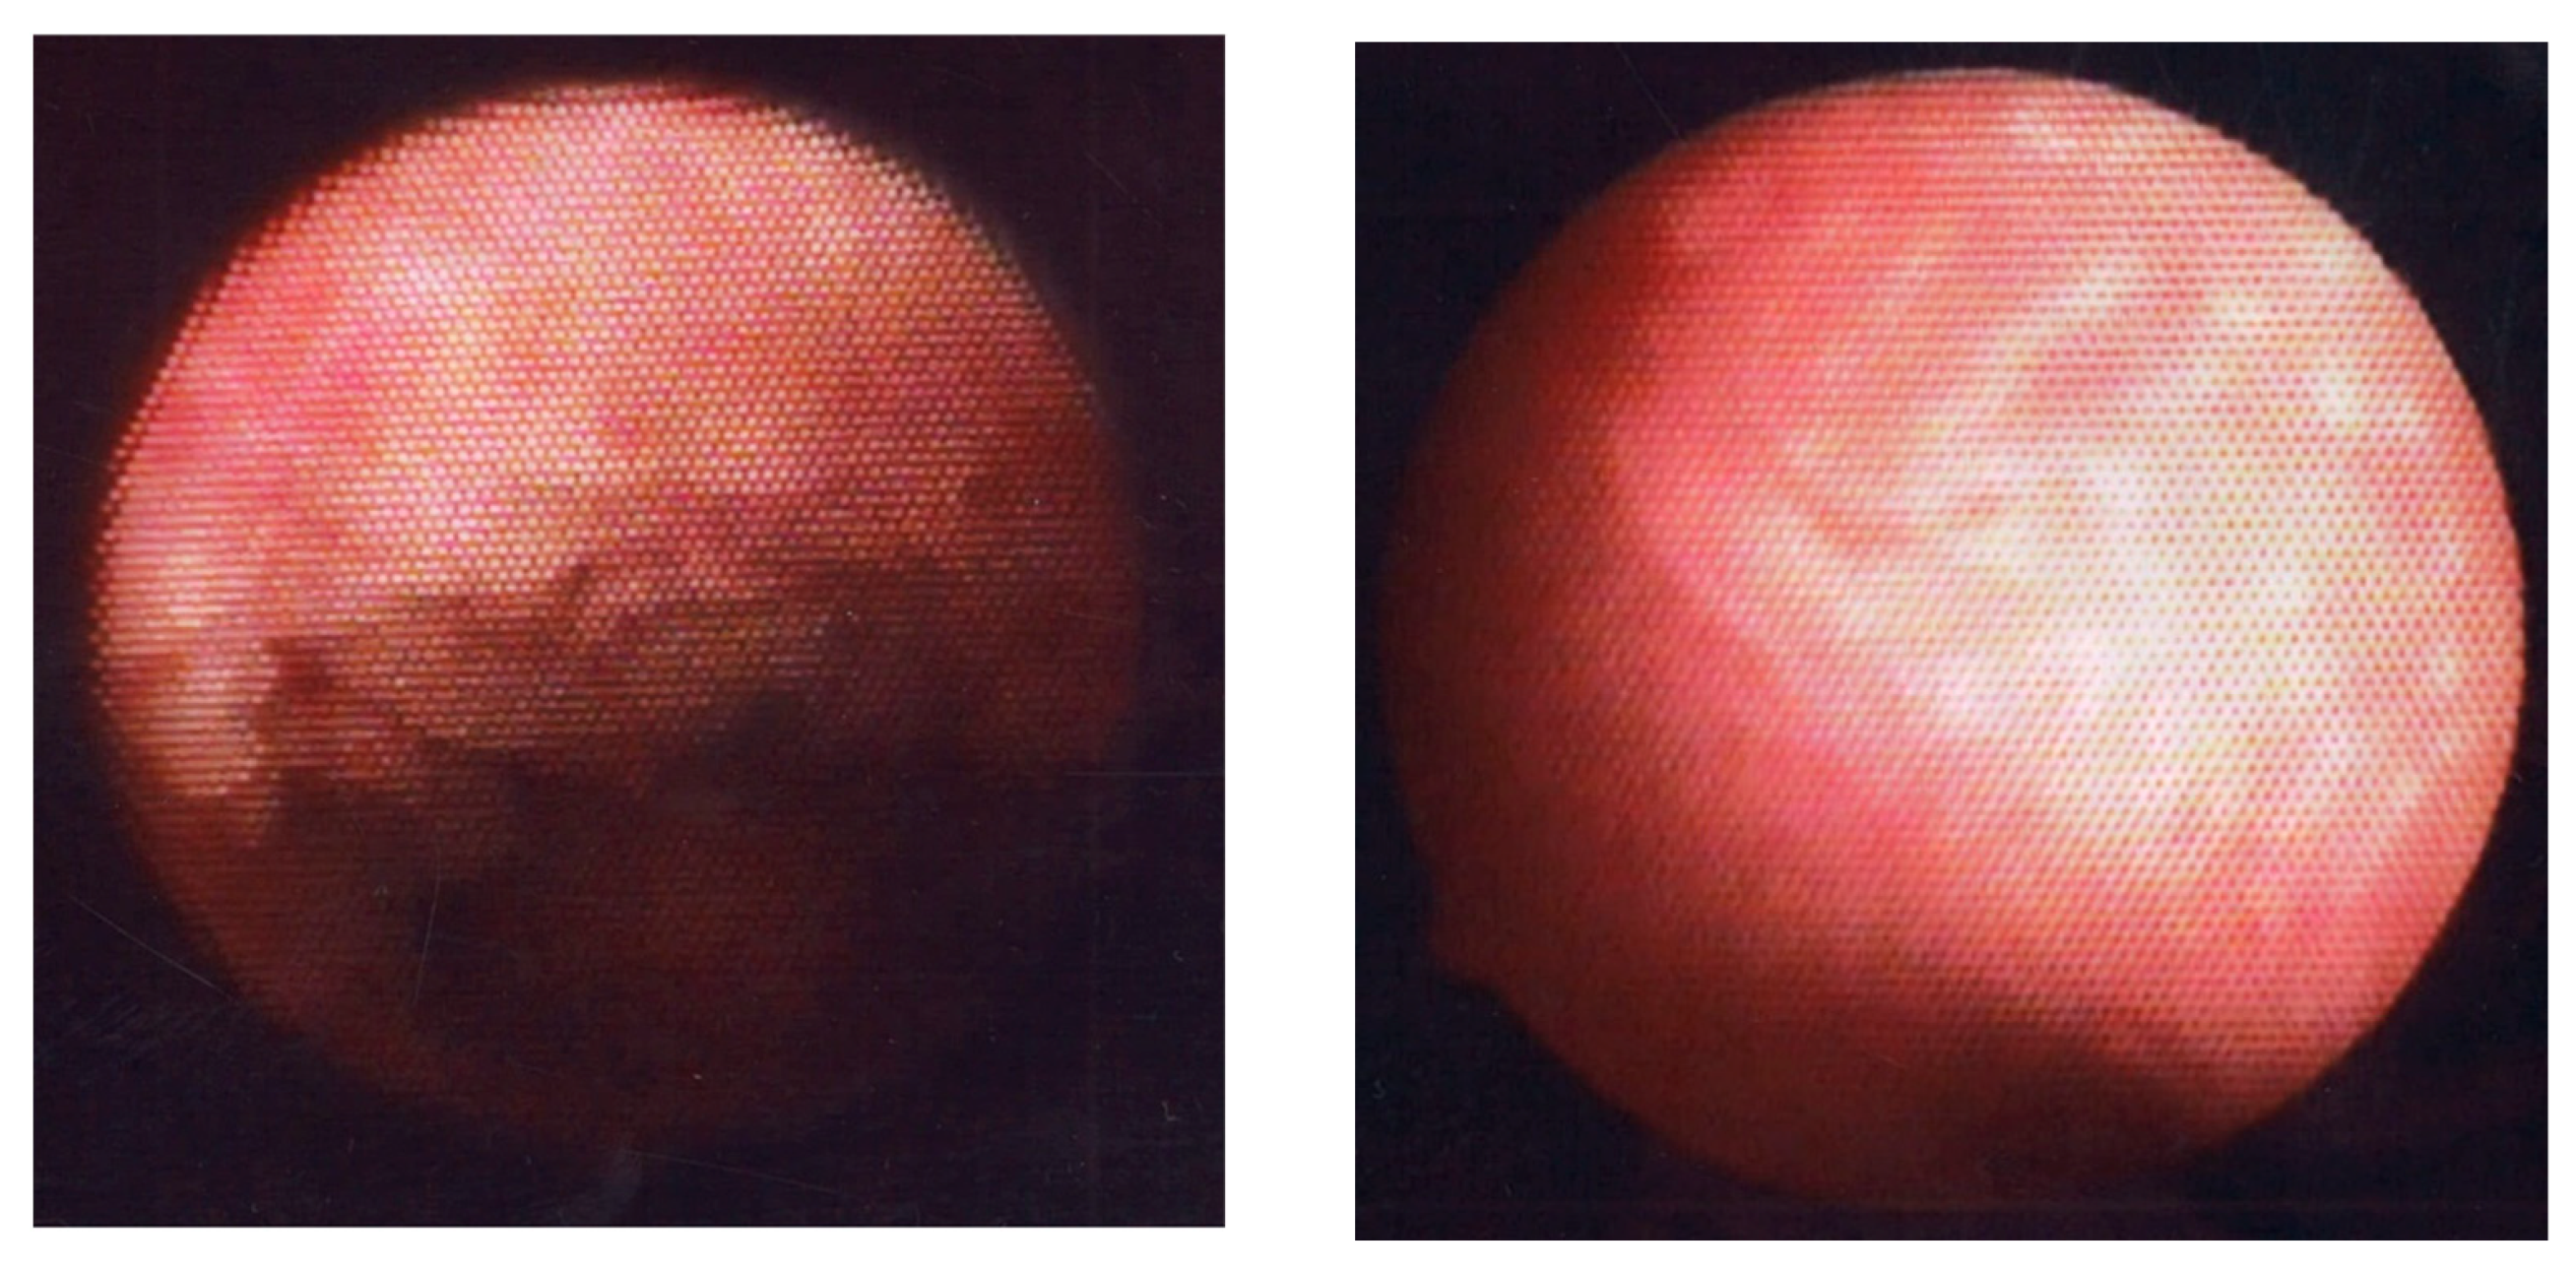

Of the five representative HysteroCE findings described above [60], endometrial micropolyposis (a cluster of typically less than 1 mm sized protrusions on the whole or focal mucosal surface, Figure 6, left panel) is the most studied and well-characterized one so far, following the first report by Cicinelli et al. [62]. They found micropolyposis in 11.7% of women undergoing hysteroscopy due to any gynecologic indications. Micropolyposis unexceptionally coexisted with other HysteroCE findings. In 93.7% of women with micropolyposis, HistoCE (based on ESPC infiltration) was identified with conventional tissue staining, in striking contrast with only 10.8% of women without micropolyposis having HistoCE. Considering all cases of HistoCE, micropolyposis was detected in 53.6% of the cases. Overall, they concluded that the diagnostic accuracy for HistoCE in the presence of micropolyposis rises to 90% (sensitivity 54%, specificity 99%, positive predictive value 94%, and negative predictive value 89%). Zolghadri et al. [28] also reported micropolyposis (in combination with or without hyperemia) as a hysteroCE finding with higher sensitivity (98.4%) and negative predictive values (97.82%), but with lower specificity (56.23%) and positive predictive values (63.5%) to predict the presence of HistoCE. The bias and limitations of these studies were that HistoCE was diagnosed with endometrial conventionally diagnosed specimens only.

4.2. Application of CNN Model to Diagnosis of Strawberry Aspect

Strawberry aspect (scattered large hyperemic areas flushed with white central points, Figure 6, right panel) is a HysteroCE finding that was described earlier by Cravello et al. [61]. Bouet et al. [101] reported that strawberry aspect is identified in 65% of infertile women undergoing repeated implantation failure in an in vitro fertilization program and/or unexplained recurrent pregnancy loss with HistoCE. There was a positive correlation (16–54% for sensitivity and 60–94% for specificity) between the presence of strawberry aspect and HistoCE when the finding was combined with other HysteroCE findings including micropolyposis. They also discussed that the lesions with strawberry aspect are unique to CE but are so mild that they may be potentially overlooked [101]. Wang et al. [106], detected strawberry aspect in 43.4% of infertile women with a history of repeated implantation failure in an in vitro fertilization program, which was confirmed with HistoCE (using conventional hematoxylin and eosin tissue staining, but not by immunohistochemistry for CD138). They also found that the expression level of interleukin-17 [107], a proinflammatory cytokine, in the endometrium, was higher in women with HistoCE than in those without HistoCE, whereas local expression of interleukin-10 [108], an anti-inflammatory cytokine, and transforming growth factor-β [109], a master regulator of inflammation, was lower in CE. Tsonis et al. [104] described that the diagnostic accuracy of the presence of micropolyposis, stromal edema, hyperemia, and strawberry aspect for HistoCE is 99.75%, 82.35%, 94.95%, and 94.77%, respectively, and agreed that strawberry aspect is a unique HysteroCE finding that potentially predicts the presence of HistoCE.

Figure 6. Fluid hysteroscopic images of endometrium with CE. Micropolyposis (left) and strawberry aspect (right).